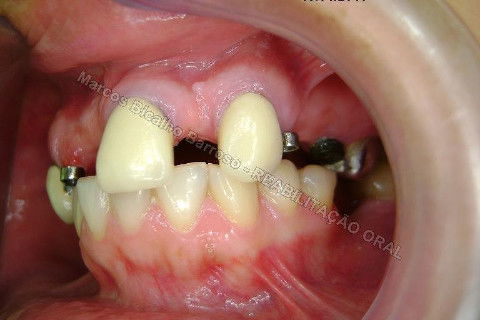

Paciente sexo feminino, 40 anos, queixava-se da situação da PPR superior, sem estabilidade, fraturas constantes nos dentes instalados. Sua vontade era resolver somente o problema da arcada superior, por questões financeiras. Logo no exame clínico inicial verifiquei a necessidade da reabiltiação inferior, pois este caso consistia em desarmonia oclusal severa, principalmente pela extrusão dos elementos 13,14 e 15 devido ausência de várias unidades inferiores. A proposta aceita pela paciente foi a instalação de 5 implantes na mandíbula + 5 implantes na maxila + tratamento endodôntico, osteoplastia e gengivoplastia nos dentes extruídos, incluindo núcleos metálicos e coroas em metalocerâmica (13,14,15). As coroas sobre implantes serão incialmente provisórias em resina fotopolimerizável e posteriormente metalocerâmica, de acordo com as possibilidades da paciente. Os procedimentos nos elementos extruídos serão apresentados em momento oportuno.